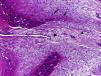

The patient is a 29-year-old woman, who complains of swelling and pain in the fifth finger of the left hand lasting for 3 months. She had no medical history and no previous trauma of the referred finger. On examination, she presented a tumor of 1.5cm×0.5cm on the tip of the finger and the subungual region, of indurated consistency which adhered to deep planes, with mild erythema and tenderness. Radiological studies showed a well-circumscribed, nodular ossified lesion with irregular borders, adhered to the l periosteum of the distal phalanx, without erosion of the cortex (Fig. 1). Laboratory studies, including biochemistry, hematology and acute phase reactants were all normal. Excision of the lesion was performed and the histopathological study revealed fibrous tissue and fibroblasts with prominent nuclei without atypia in its periphery, and immature osteoid deposits surrounded by an osteoblastic rim in the central area (Fig. 2). These findings were consistent with the diagnosis of florid reactive periostitis of the hand (FRPH). There was no recurrence of the lesion.

FRPH is a rare benign entity characterized by a lush production of osteoblastic proliferative fibrous stroma in the periosteum of the fingers.1 Its pathogenesis is unknown but is considered to correspond more to a reactive process than to a neoplasm, with a history of trauma being present in up to 50% of cases.2 Although it was described in 19333 there still is confusion in the literature caused by different denominations, including paraostal fasciitis, ossifying fasciitis, fibro-osseous pseudotumor, pseudomalignant bone tumor of the soft tissue of the fingers and nodular fasciitis, with FRPH being the accepted term.2,4 It is most frequently located in the proximal phalanx, followed by the middle phalanx, metacarpal joints and distal phalanx; it is rare in the first two fingers. It usually occurs in women during the second and third decades of life, and is clinically characterized by swelling, pain and erythema of the affected finger.2,5 Radiographs show increased soft tissue and periosteal new bone formation, which may have a lamellar or mature bone5 appearance. The cortex is usually intact, although erosions have been occasionally described.6 The differential diagnosis includes infections (septic tenosynovitis, soft tissue abscess with bone involvement, cortical osteomyelitis), myositis ossificans, benign tumors such as giant cell tendon sheath tumors and osteochondroma, and malignant ones such as the paraostal and periosteal osteosarcoma, synovial sarcoma and periosteal chondrosarcoma.1,5 The recommended treatment is local excision, which is curative in most cases.5 In conclusion, although FRPH is an uncommon lesion, it should be taken into account because it can simulate other more serious conditions such as malignant bone neoplasms.